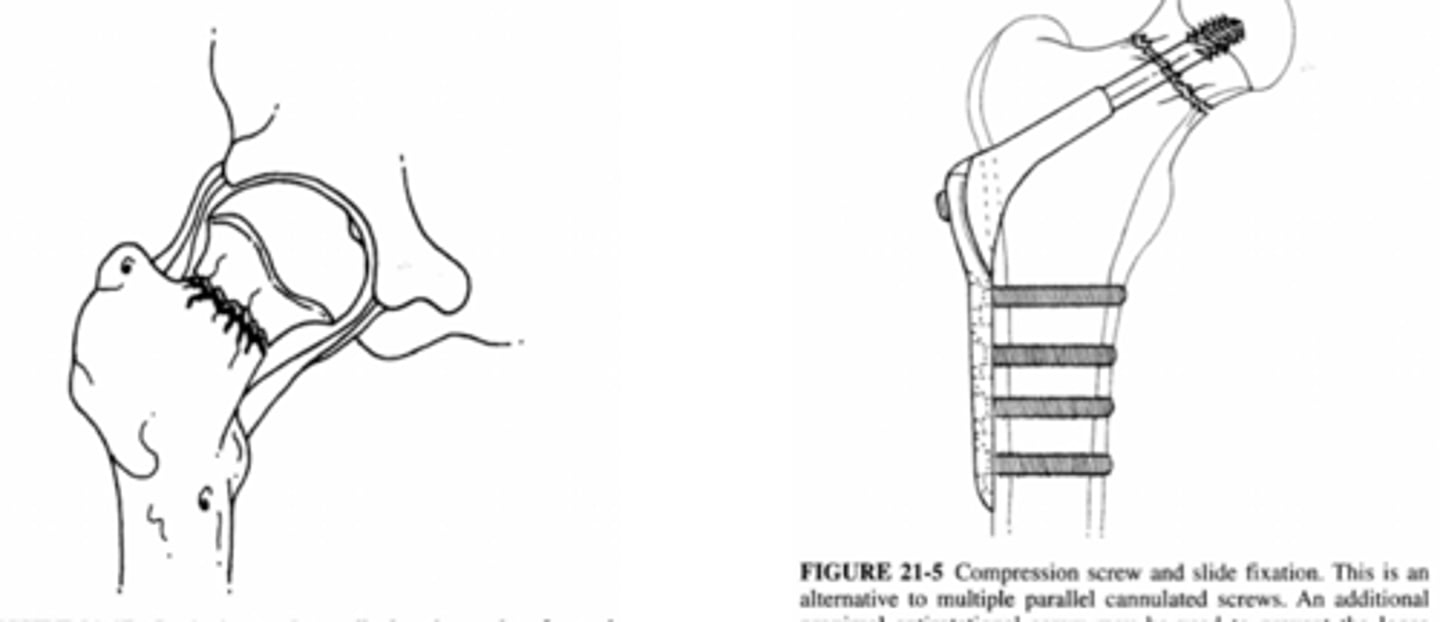

trochanteric osteotomy

used for THA revisions

intertrochanteric fx

intertrochanteric fx

Comminuted intertrochanteric fracture. There is a fracture from the greater to the lesser trochanter (blue arrow). There are separate fragments of the greater trochanter (white arrow) and lesser trochanter (red arrow). There is varus deformity (white line) of the femoral shaft.